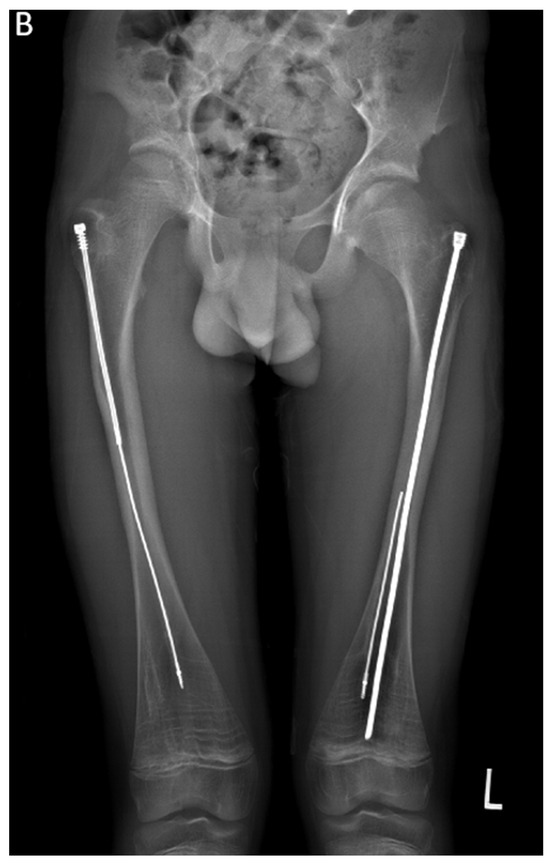

In the second case presented in this paper, a 15-year-old boy diagnosed with OI type IV, who was previously operated on 12 years ago with bilateral FD rods, presented to his regular clinic visit with pain over the left greater trochanter. This patient was ambulating without any braces or aids and was functioning very well. He did not sustain any fractures since the FD rod insertion, and full ROM of his hips was maintained. X-ray showed a completely disengaged FD rod on the left side, where the female component migrated distally and laterally across the lateral cortex. The protruding proximal part of the female component was the site of the pain and tenderness (Figure 10A). On the right side, the FD rod was almost disengaged, and a mild deformity was present anterolaterally. The X-ray demonstrates that the intramedullary canal is too narrow to accommodate an adult-sized nail. As the patient had almost reached skeletal maturity, it was decided not to use another telescoping rod but instead to use a non-telescoping SLIM nail. Because the distal male component of the existing FD rod was situated deep into the canal, making its retrieval problematic, it was decided pre-operatively to leave it in situ and insert the new rod beside it. The female component on the left side needed to be removed, and a solid SLIM rod was inserted to protect the bone (Figure 10B). Revision to a non-telescoping rod was considered for the right side as well; however, surveillance was opted for as the patient was approaching skeletal maturity. In this case, the indication for use of the SLIM nail is a near skeletally mature patient, therefore, not requiring a telescoping nail. However, the intramedullary canal was too narrow to accommodate a larger solid nail.

Figure 10.

(A)—Pre-operative X-ray. (B)—Post-revision X-ray showing installed SLIM nail in the left femur.